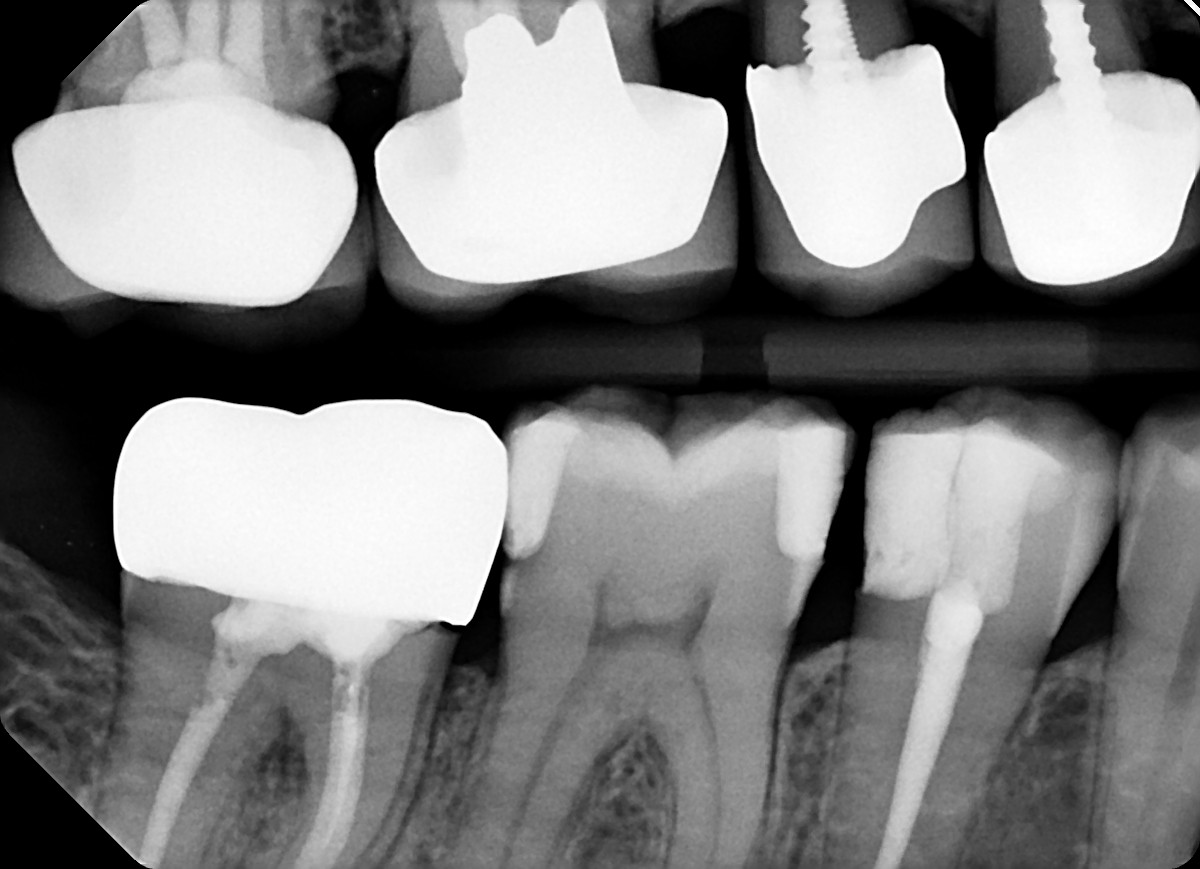

1. What option can explain the crown of the tooth # 1.4?

3. What option can explain the crown of the tooth #3.6?

4. What option can explain the crown of the tooth #4.7?

5. What option can explain the crown of the tooth #2.6?